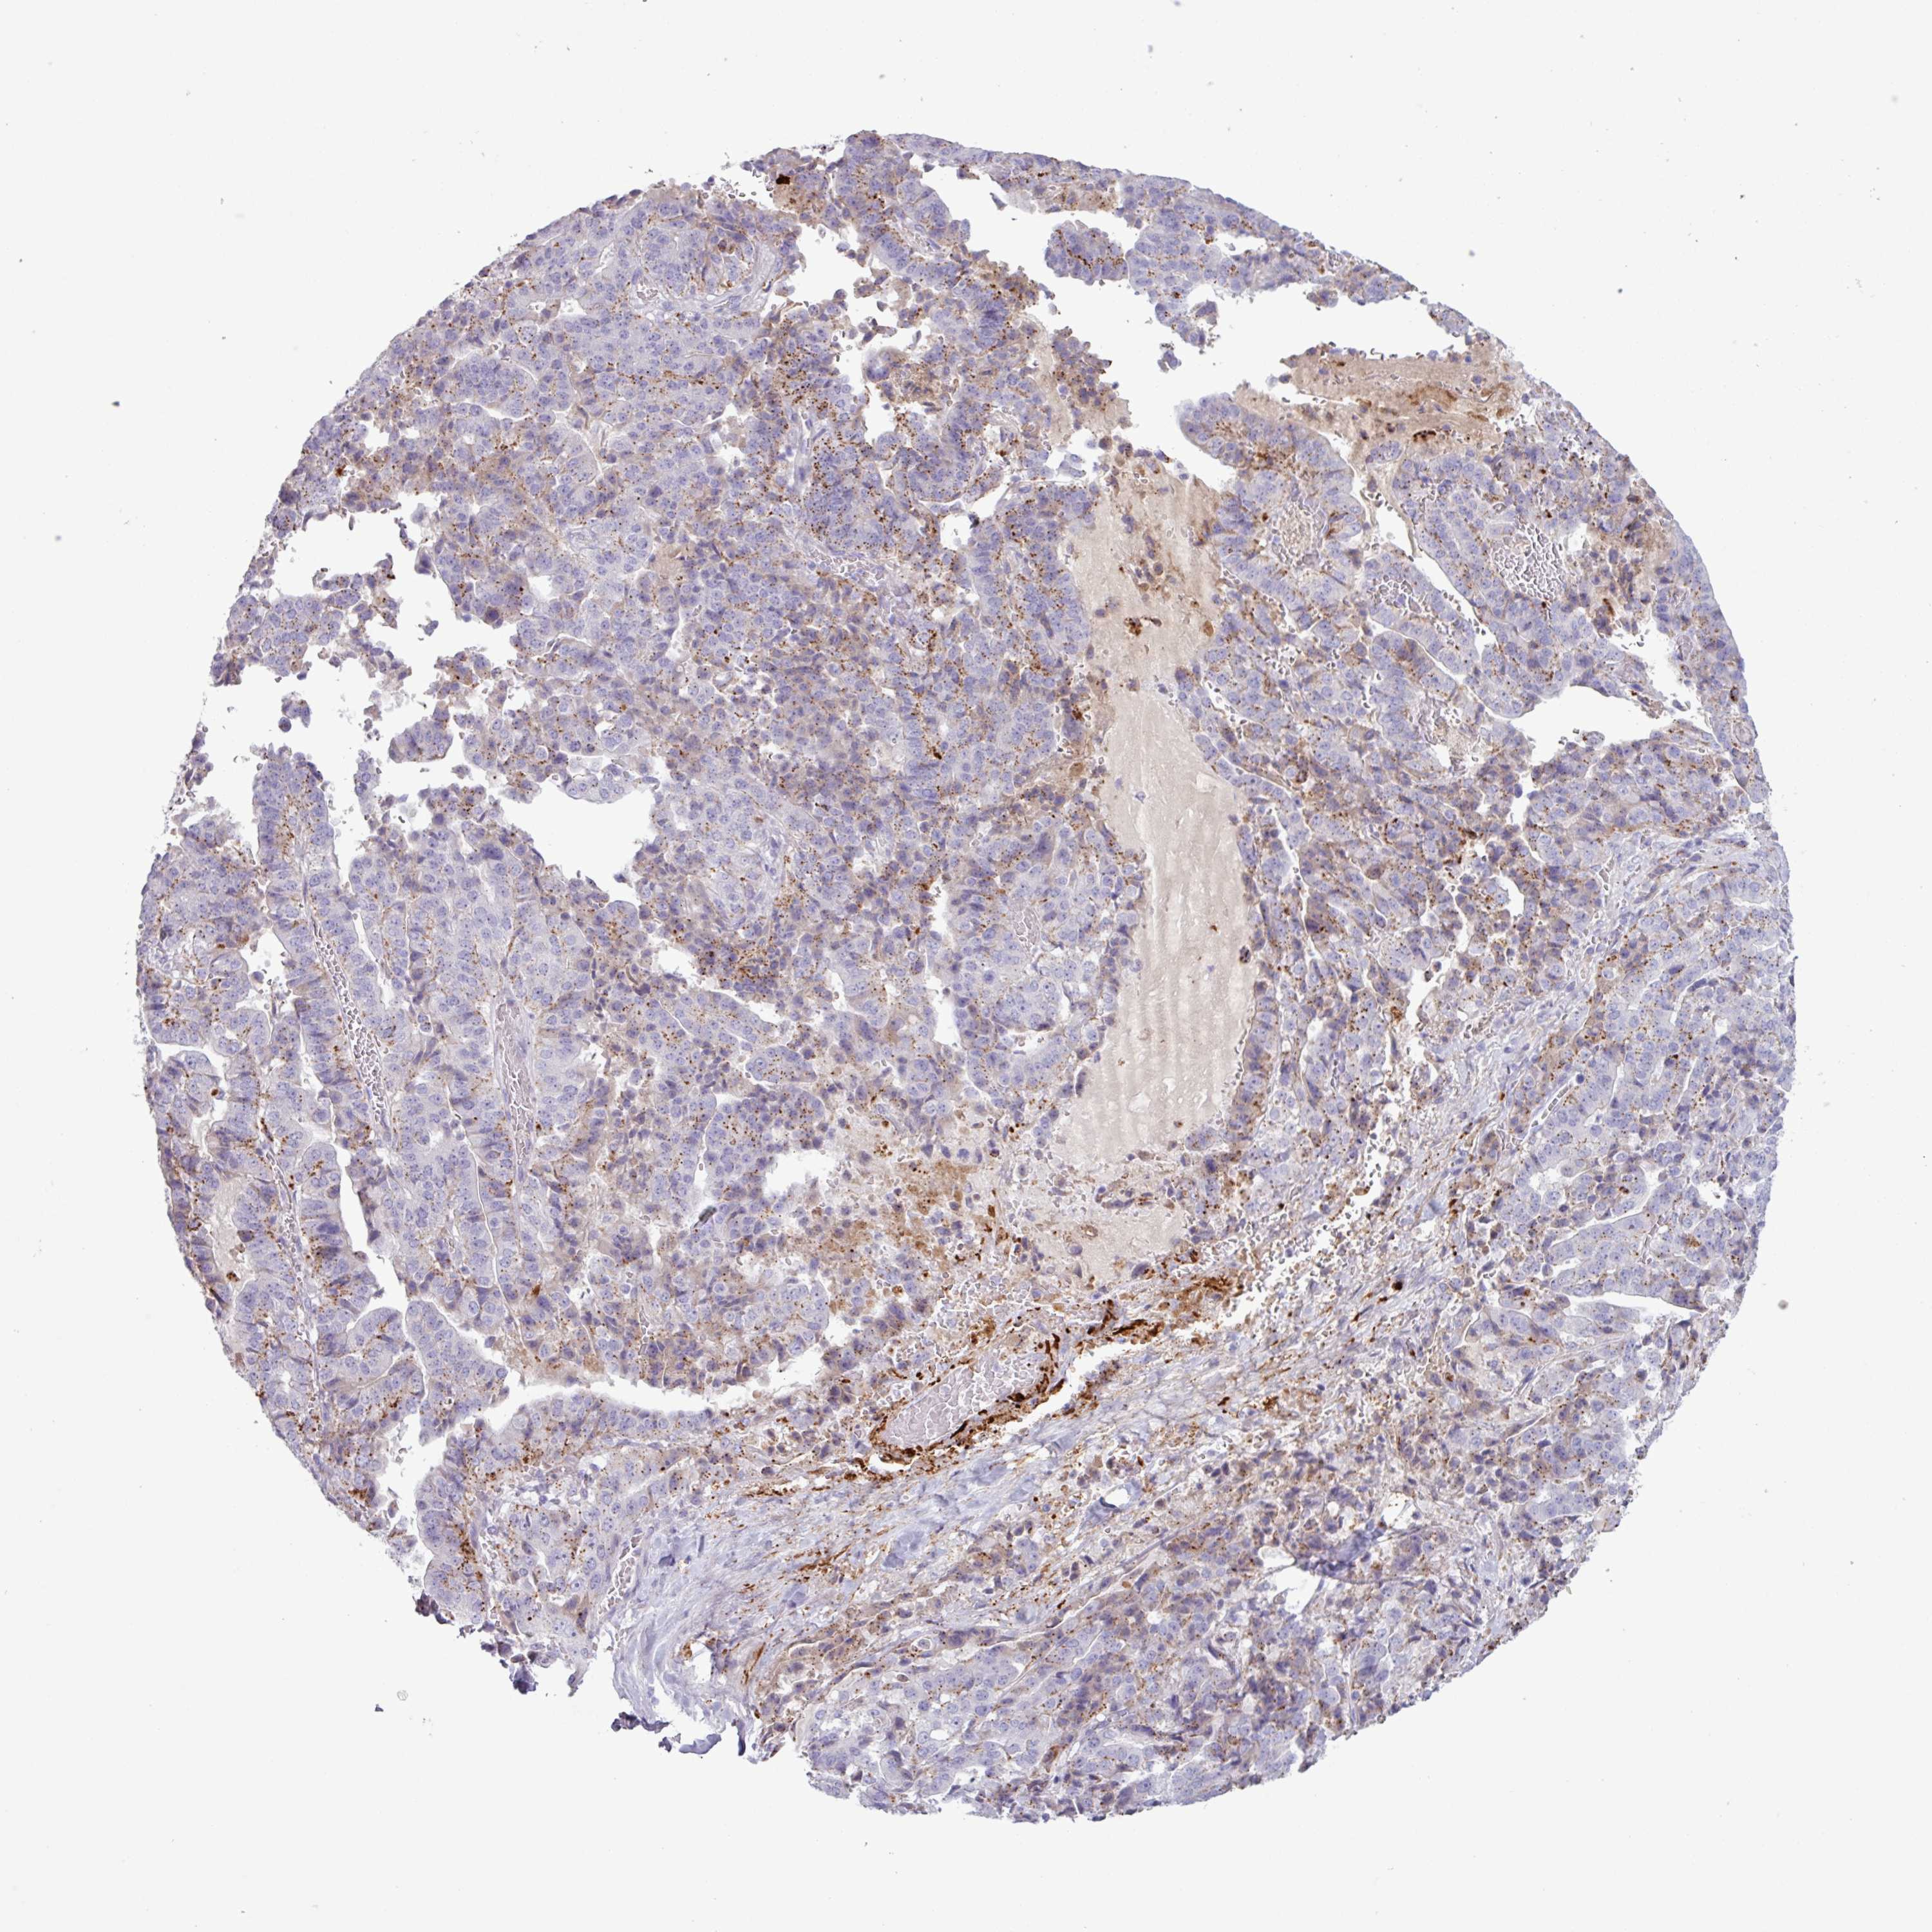

STOMACH CANCER - Protein expressioni

A mouse-over function shows sample information and annotation data. Click on an image to view it in a full screen mode. Samples can be filtered based on level of antibody staining by selecting one or several of the following categories: high, medium, low and not detected. The assay and annotation is described here.

Note that samples used for immunohistochemistry by the Human Protein Atlas do not correspond to samples in the TCGA dataset.

Antibody stainingi

Antibody staining in the annotated cell types in the current human tissue is reported as not detected, low, medium, or high, based on conventional immunohistochemistry profiling in selected tissues. This score is based on the combination of the staining intensity and fraction of stained cells.

Each image is clickable and will lead to virtual microscopy that enables deeper exploration of all samples and also displays staining intensity scores, fraction scores and subcellular localization as well as patient and tissue information for each sample.

Adenocarcinoma, NOS